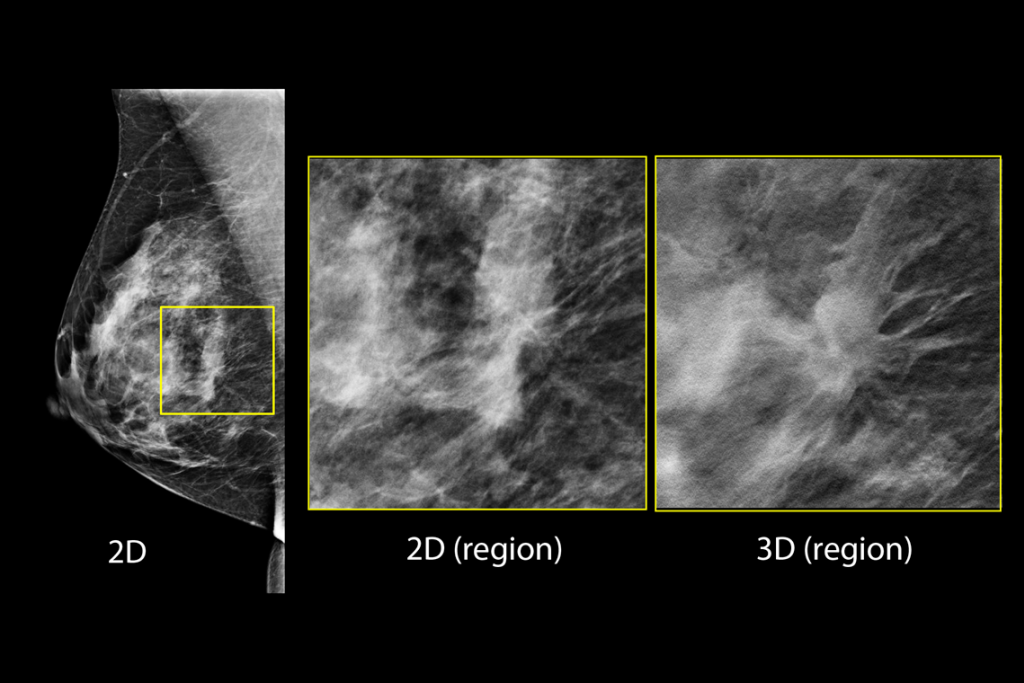

Imagens clínicas de mamografia com lesão suspeita